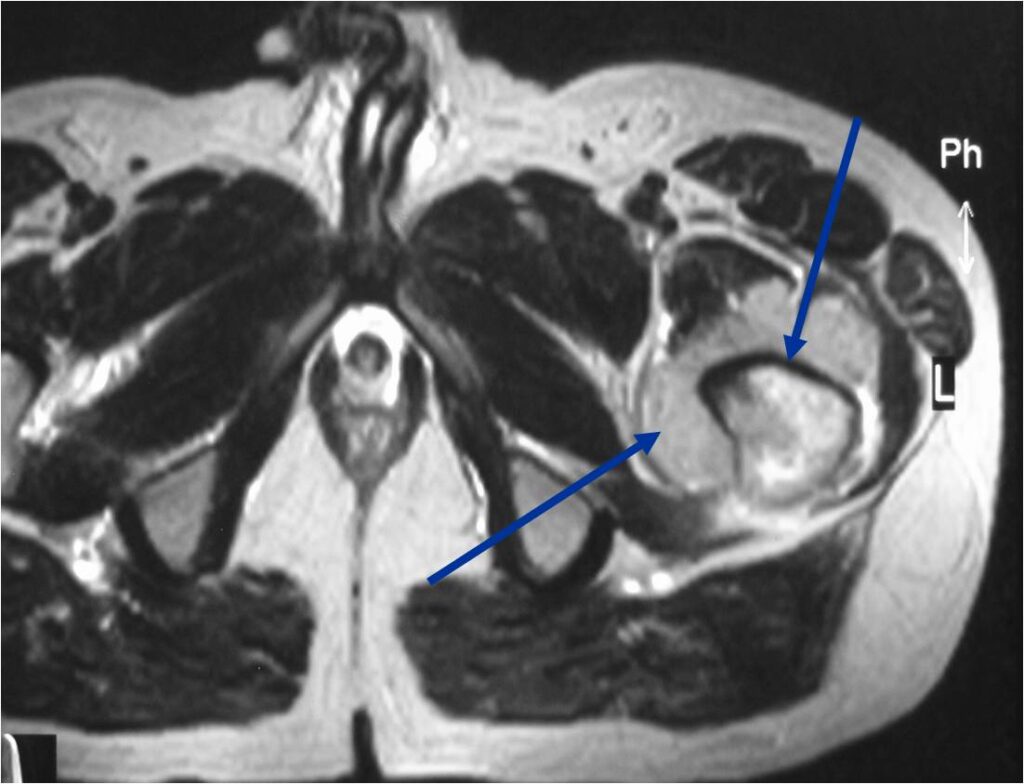

- Soft tissue mass— by CT (80%); by MRI (100%)

- Diffuse infiltrative growth pattern with soft tissue extension

- Extraosseous tissue

- Tan or white, resembles lymphomatous lymph nodes

- Areas of necrosis, hemorrhage, and cystic degeneration are present